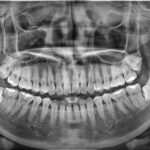

Chuyện là trước khi sắp qua Hàn mình có đi khám nha khoa tổng quát, thì chụp và phát hiện ra 2 quả răng khôn bên dưới “ngu” quá🥲. Nhưng mà gần ngày bay lắm rồi nên không có can đam nhổ. Một phần cũng vì bác sĩ ở Việt Nam bảo ca mình rất khó và nguy hiểm. Đây cho các bạn xem ảnh chụp X- quang luôn